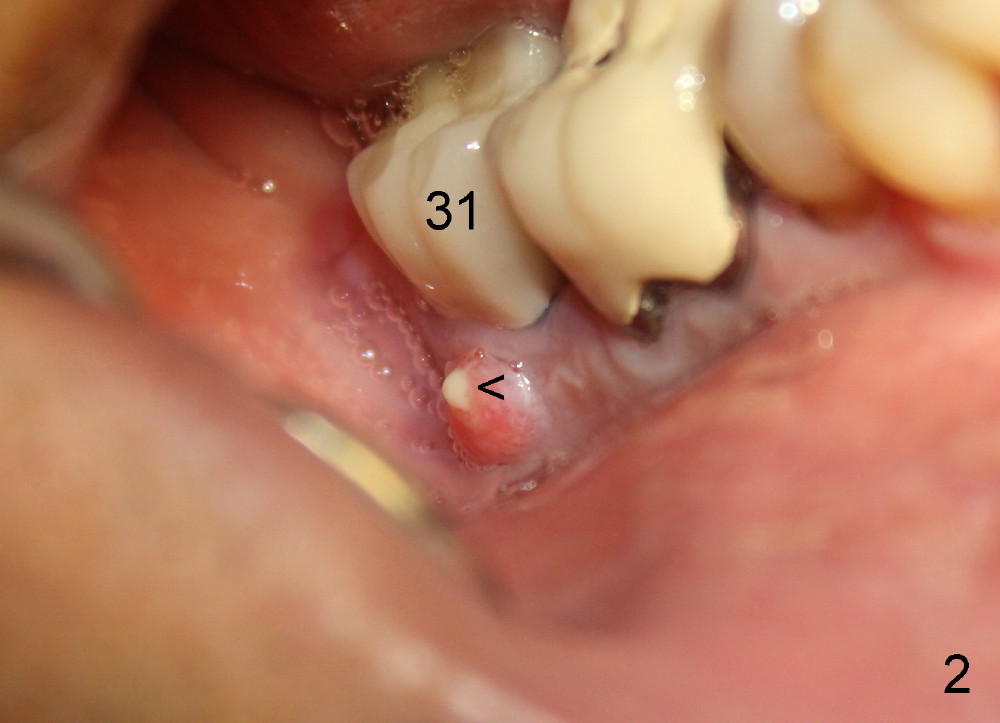

A 51-year-old man has experienced pain and swelling in the lower right 2nd molar for 7 months (Fig.1, P: post in the mesial root; <: gutta percha inserted into a buccal fistula). Fig.2 is taken immediately before extraction (<: purulent discharge from the mesiobuccal fistula) and immediate implant (Fig.3 implant design: 7x14 mm). A vertical root fracture is noted in the mesial root (Fig.4: lingual view). The septum is in fact absent, as compared to Fig.1. The mesiobuccal plate is low; the osteotomy starts lingual to the center of the socket. Fig.5 shows a 4.5x17 mm tap in place: approximately 3.5 mm in the new bone (~2.5 mm from the inferior alveolar canal). When a 7x17 mm tap (14 mm from the gingival margin) is placed in the socket, it looks relatively small. Fig.6 shows a 8x14 mm implant in place with a small gap distally. Mineralized cancellous allograft and Osteogen mixture is placed mainly buccally, followed by a thin strip of collagen dressing and sutures (Fig.7); an abutment (A) is placed to keep perio dressing in place. The perio dressing does not stay long. The buccal portion dislodges by itself 5 days postop. The lingual portion is removed in clinic. New dressing is going to be re-applied, because the buccal wound has not completely healed (Fig.8 <, albeit asymptomatic) with partial exposure of the bone graft (*). Why is the dressing lost so early? The abutment is not long enough; there is plenty of occlusal clearance (Fig.9 arrows). A longer abutment is used to increase mechanical retention for perio dressing (Fig.10). By the time the second perio dressing dislodges, the wound has healed (Fig.11, 13 days postop).